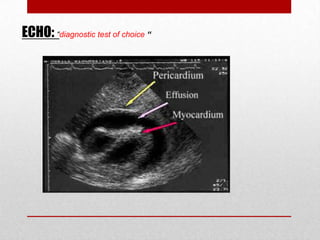

ECHO: “diagnostic test of choice “